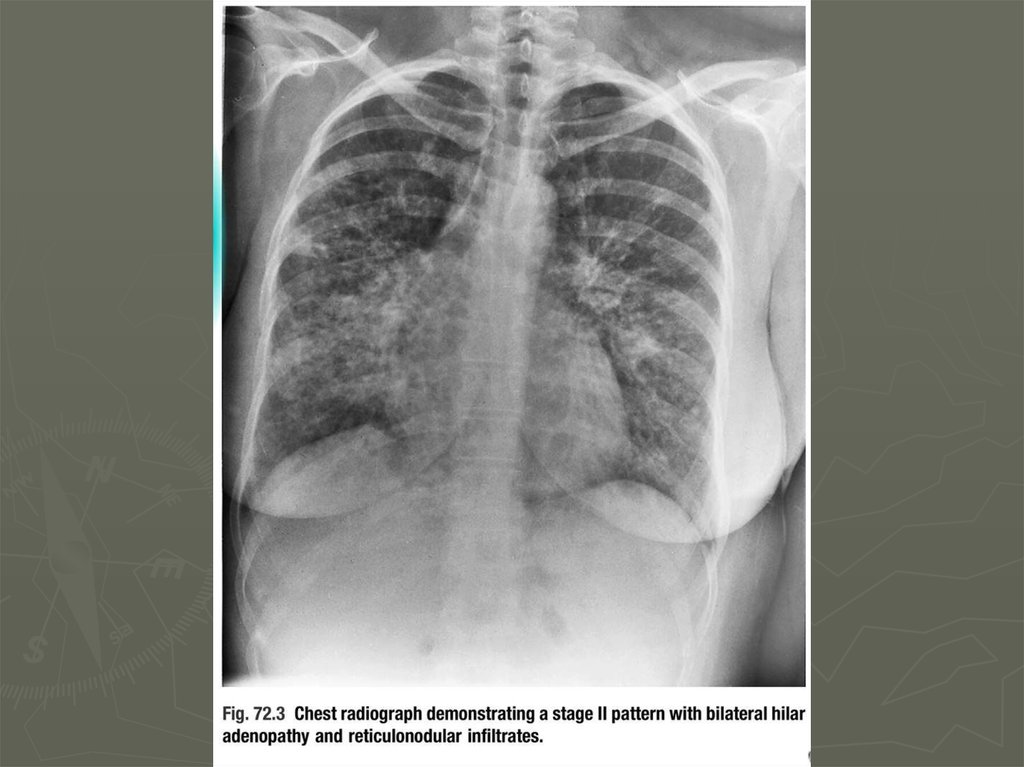

10. Диагностика

11. Диагностика